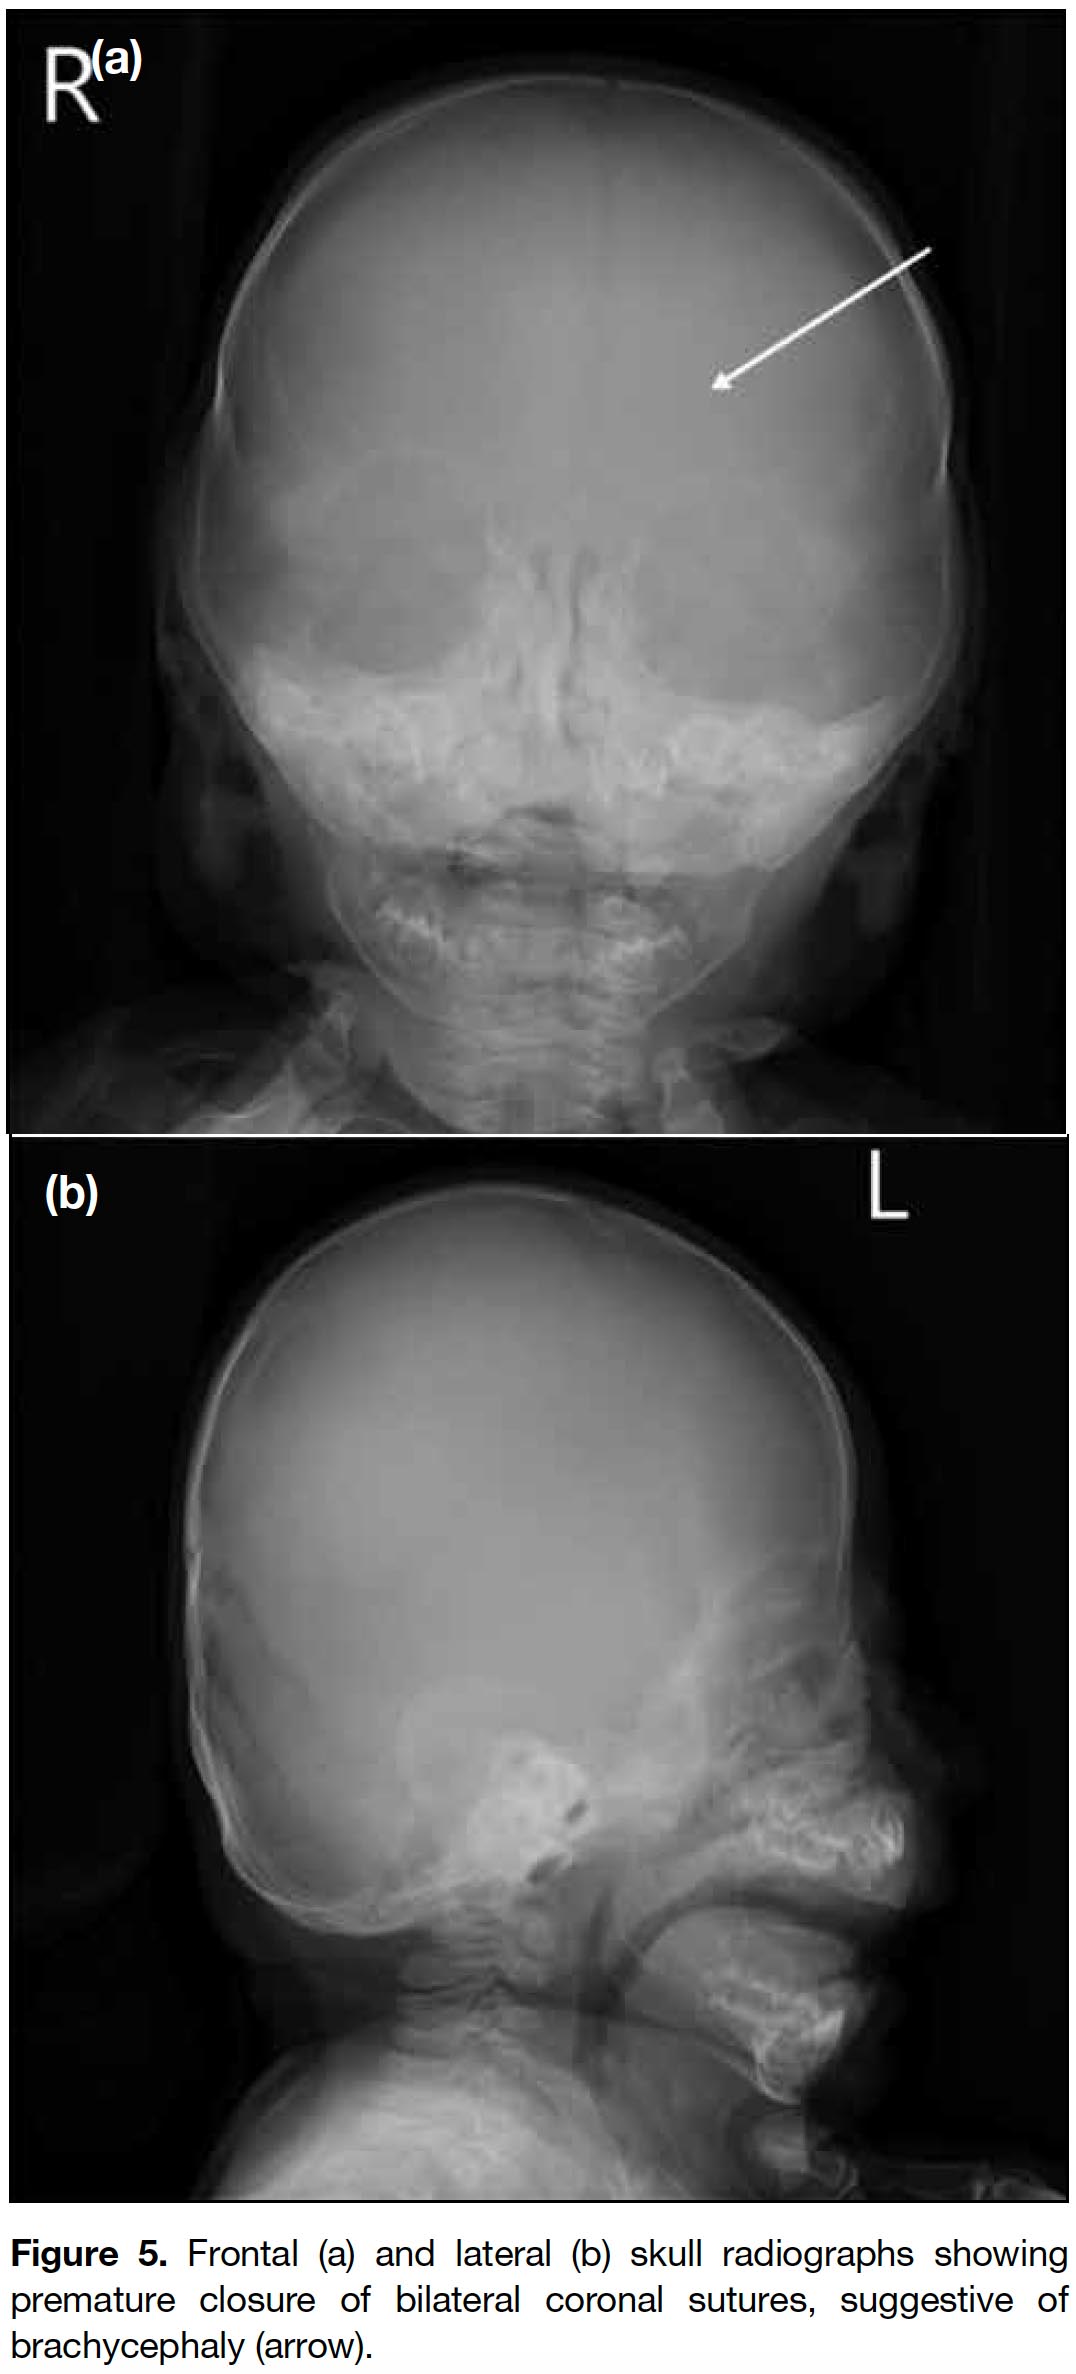

Figure 5. Frontal (a) and lateral (b) skull radiographs showing premature closure of bilateral coronal sutures, suggestive of brachycephaly (arrow).

Radiological findings of I-cell disease include dysostosis multiplex, a characteristic constellation of radiographic appearance describing the progressive skeletal dysplasia. These changes can be seen in the newborn period and include J-shaped sella turcica; widened ribs at or near the costochondral junctions and narrow dorsal juxtavertebral parts of ribs, namely oar-shaped ribs; vertebral body deformity with superior notching and anteroinferior beaking especially in the lower thoracic and upper-lumbar region; kyphosis and gibbus deformity of the thoracolumbar spine; flaring of the iliac wings with constricted inferior iliac bodies; slanting acetabular roofs and coxa valga; coarse bony trabeculation; hypoplastic/dysplastic capital femoral epiphyses; delayed epiphyseal ossification; bullet-shaped proximal phalanges and proximal pointing of the metacarpals; diaphyseal widening and expansion of tubular bones; metaphyseal cupping and fraying that resemble rickets.[7,8] These features are also present in other type of storage disease, primarily the mucopolysaccharidoses. Some studies have reported findings of cloaking, a transient phenomenon in infants and rarely detectable after the first year, combined with certain radiographic findings in the perinatal/newborn infant period suggestive of I-cell disease. These include talocalcaneal stippling, sacrococcygeal sclerosis, severe generalised vertebral body sclerosis, vertebral body rounding of the lower thoracic/lumbar spine, and rickets/hyperparathyroidism-like changes.[4,9] Other prenatal sonographic abnormalities of I-cell disease have also been reported and include oligohydramnios, intrauterine growth retardation, echogenic cardiac foci, and short femurs and transient alveolomaxillary defect.[3,10] Our patient exhibited most of the imaging features of dysostosis multiplex, including the very characteristic (almost diagnostic) abnormality of cloaking periosteal reaction and characteristic rounding of the thoracic and lumbar vertebrae.[9] In addition, bilateral coronal craniosynostosis was present in our case. This is not commonly seen and only a few cases have been reported. There remains debate about whether it is a component of I-cell disease.[3]